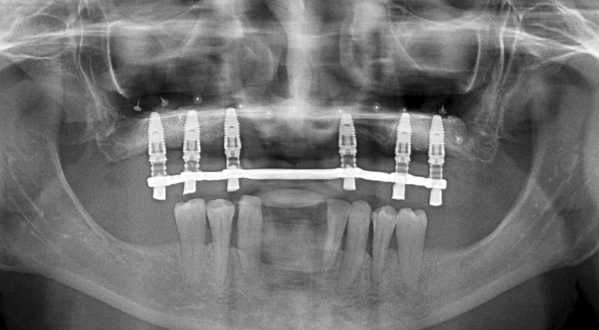

Full Arch Immediate Implant Treatment with 4 BLX Straumann Implants with 3D Printed Hybrid Prostheses in a Failed Lower Dentition Case